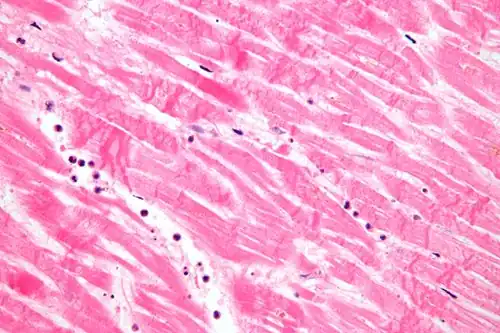

Fascicular: Generally the same cell type throughout, but some form band-like groups that are aligned in the same direction.

Fascicular: Generally the same cell type throughout, but some form band-like groups that are aligned in the same direction. -